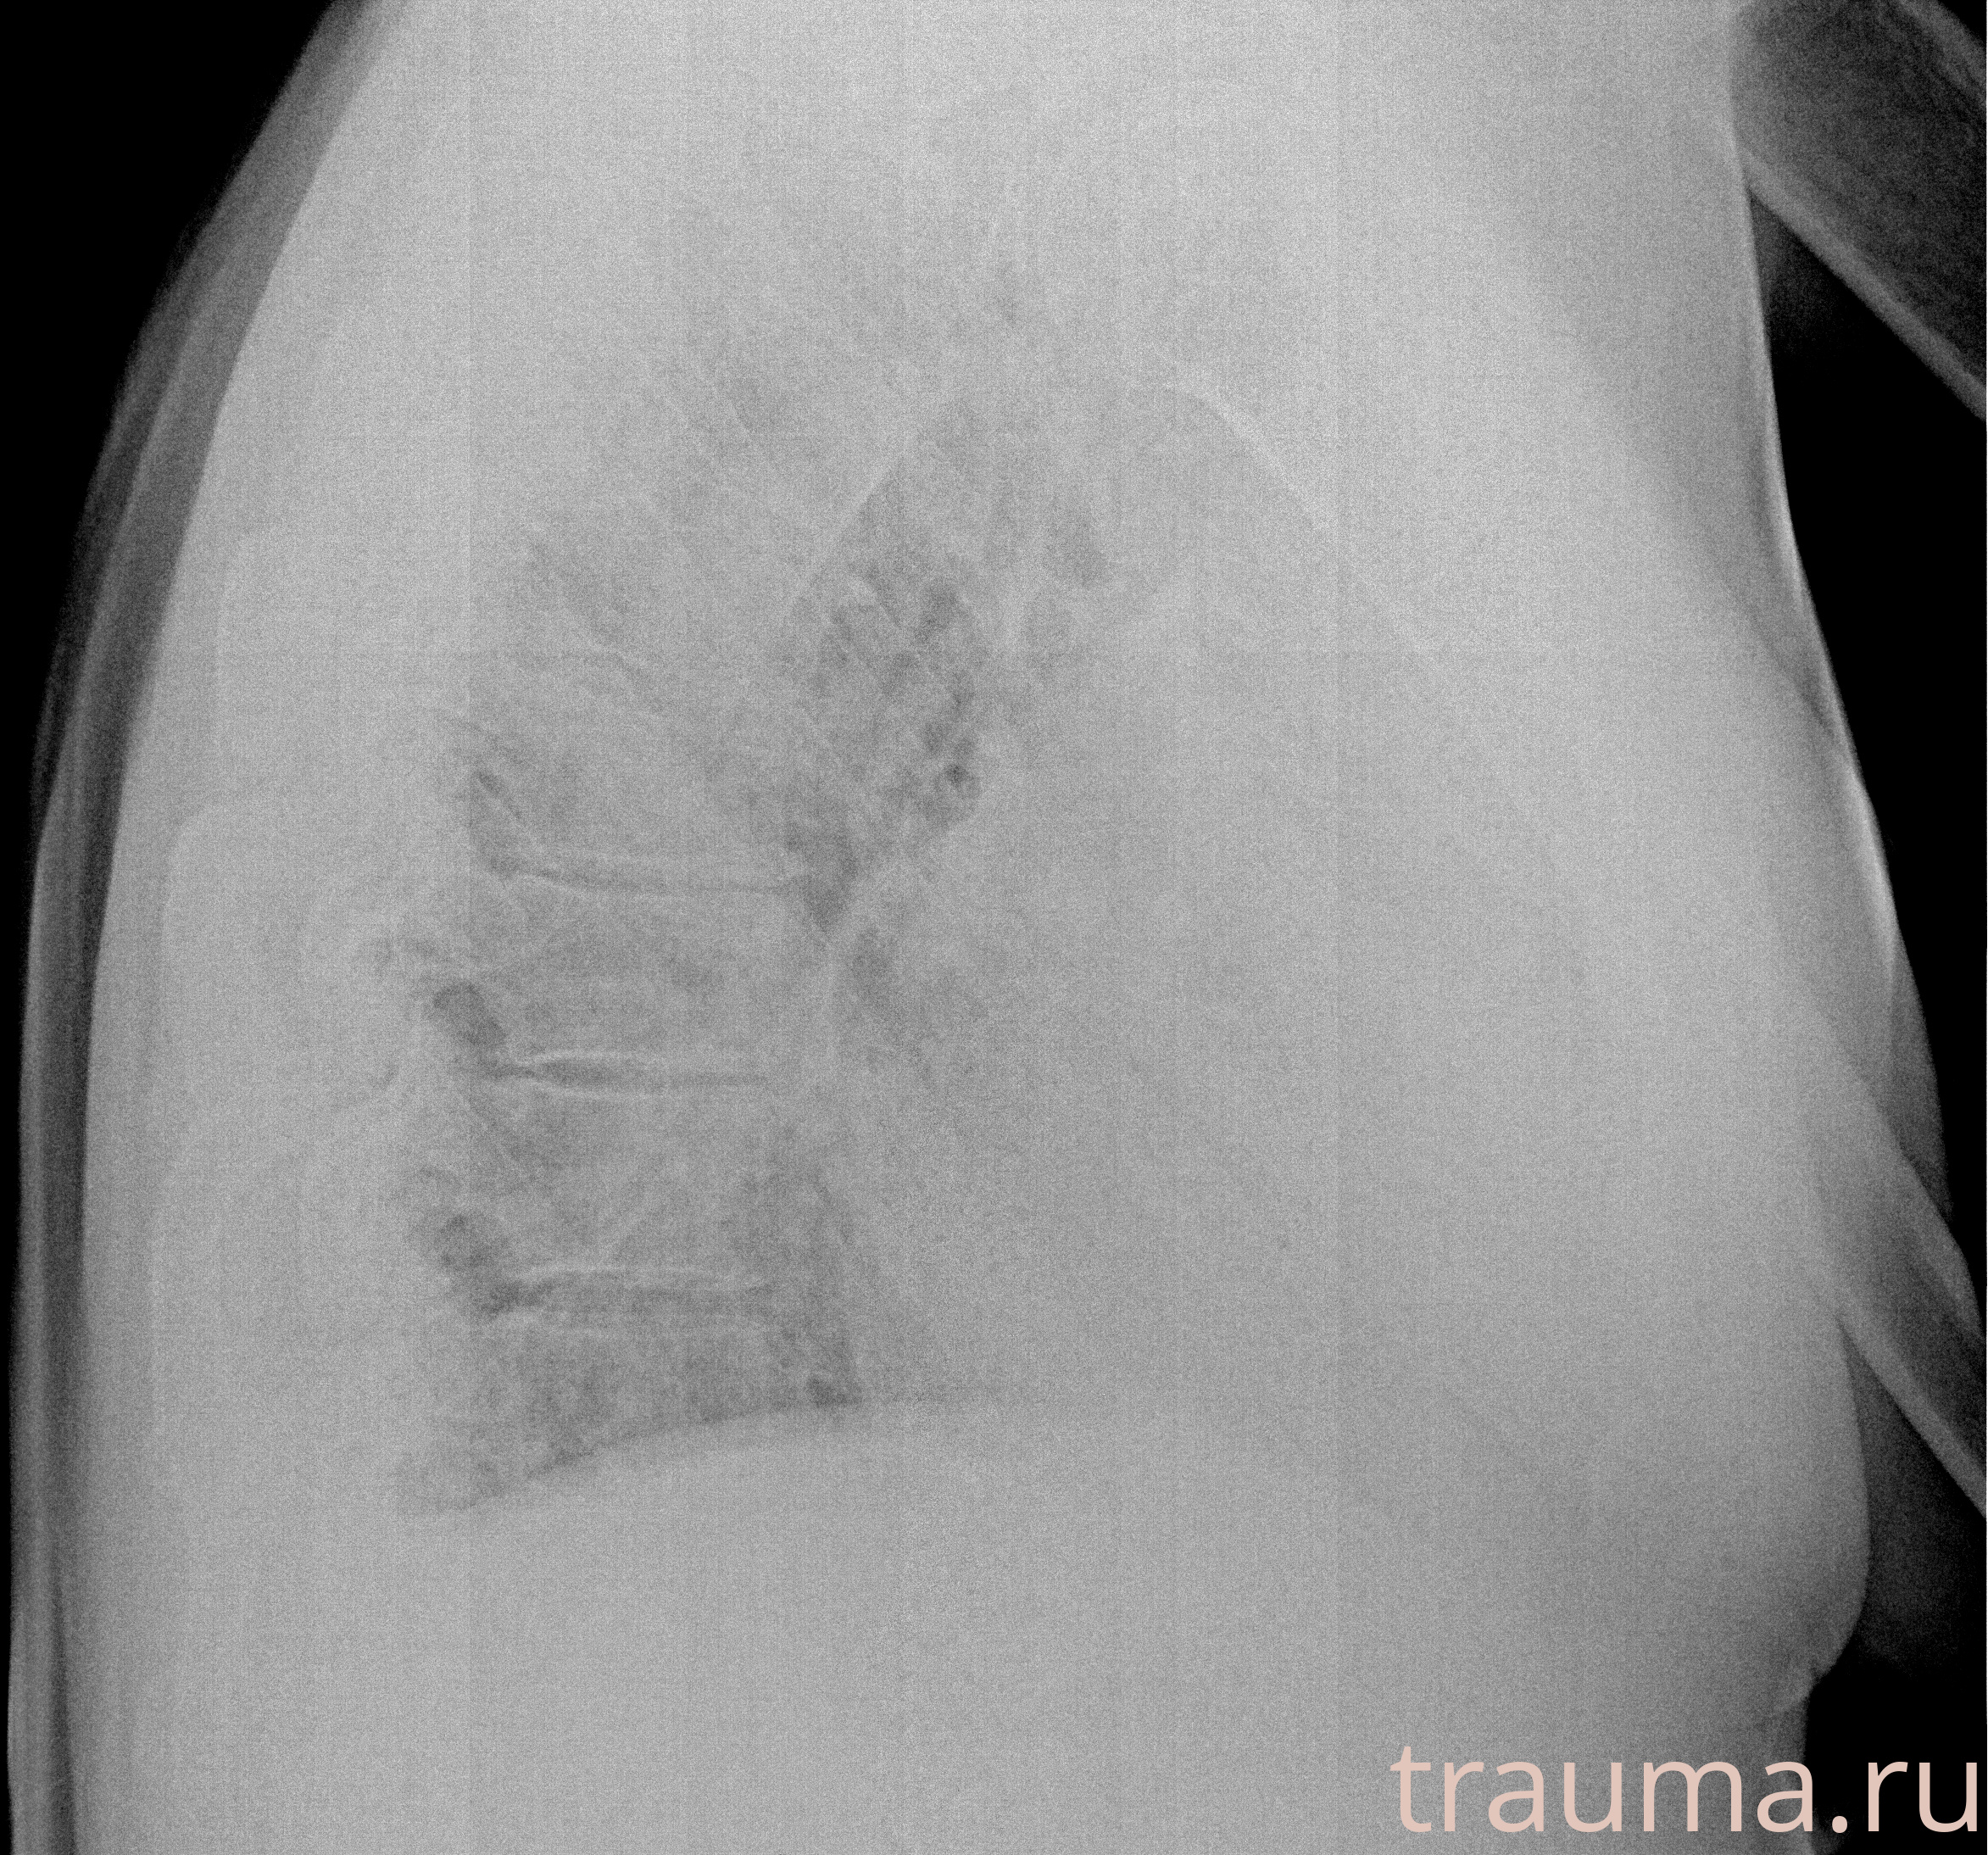

Рентгенограммы

Рентген на дому: по вашему адресу приезжает врач-рентгенолог, травматолог-ортопед с мобильным рентгеновским аппаратом, проводит диагностику травмы или заболевания, делает необходимые рентгенограммы, дает рекомендации по дальнейшему лечению. Получить качественные снимки в домашних условиях возможно благодаря уникальной методике, разработанной МосРентген Центром для института  Склифосовского

Яркость: 1   Контраст: 1   Инвертировать: 0 Увеличение: 1

Перетаскивайте мышь вверх/вниз для контраста, влево/право для яркости. Прокрутка колесом изменяет масштаб. Нажмите Сбросить для возврата к исходному изображению. При увеличении держите мышь в той области, которую хотите рассмотреть.